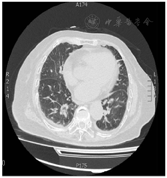

患者,女性,84岁,因"反复胸痛1周,持续加重8 h"于2021年8月17日急诊收治入院。既往无高血压、糖尿病病史。入院查体:血压105/56 mmHg(1 mmHg=0.133 kPa),神清,气略促,对答切题,颈软,颈静脉无怒张,双肺呼吸音粗可闻及较多的湿啰音,心率112次/min,律齐,各瓣膜区未闻及病理性杂音,腹平软,无压痛,反跳痛,肝脾肋下未及。双下肢轻度浮肿,四肢肌力正常,病理征(-);急诊心电图示:急性广泛前壁心肌梗死(图1);胸部CT提示双侧间质性肺水肿可能(图2);实验室检查:肌钙蛋白T:3.13 μg/L,肌酸激酶同工酶:188.93 μg/L,D二聚体:1.36 mg/L。根据患者病史、心电图及心肌酶学明确诊断为急性ST抬高型心肌梗死,予以术前嚼服负荷量绿色通道行急诊再灌注治疗,冠脉造影示:前降支次全闭塞,远端TIMI血流0级,回旋支近端40%~50%局限性狭窄,TIMI血流3级,右冠起源左冠窦,无狭窄,TIMI血流3级,于前降支近端植入3.0 mm×18 mm Firebird 2支架一枚(附件冠脉造影+PCI图3、视频1)后安返CCU。继续予以心电及血流动力学监测,动态监测心电图及酶学改变,阿司匹林、替格瑞洛抗血小板聚集,他汀调脂、稳定斑块,扩管利尿改善心功能等治疗。3 h后患者突发血压下降为60/40 mmHg,四肢湿冷,动脉搏动弱,意识尚清,指末氧饱和度95%,心电监测提示窦性心动过速,心率130次/min。立即予以平衡液扩容,多巴胺+去甲肾上腺素提升血压,留置颈内静脉置管监测CVP,股动脉置管监测有创动脉压。床旁心超提示微量心包积液,右房室内径偏小(37 mm×18 mm,40 mm×22 mm),左室壁多壁段运动异常,EF35%(图4),床位医师考虑容量不足,继续补液扩容及血管活性药物升压,但患者血压仍未见回升;再次复查心超提示心包积液较前明显增多,未见室壁不连续及异常血流信号,考虑心包填塞(图5),立即行心超定位剑突下心包穿刺,引流出暗红色不凝血,予以心包置管留置引流出血性液体300 ml,患者血压恢复至119/49 mmHg,心率95次/min,再次复查心超示左室心尖处见几束细丝状异常血流信号局限于纤维膜状回声内,考虑左室心尖破裂伴假性室壁瘤可能性大(图6)

根据以上3条可以明确诊断为急性ST抬高型前壁心肌梗死,患者冠脉造影亦证实本诊断成立。患者查体无休克征象,入院血压105/56 mmHg,双肺较多湿罗音,胸部CT提示双侧间质性肺水肿可能,故按Killip分级为Ⅲ级。